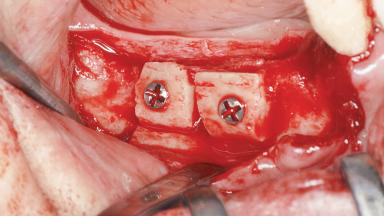

A woman in her mid-fifties was referred by a dental student for dental implant placement. Both posterior segments of the mandible had been edentulous for more than 4 years, the only residual tooth being the right lower first premolar. The patient had used a removable partial denture but was not entirely satisfied with its function. The clinical examination revealed a sharp edentulous ridge in both posterior segments of the mandible, and the patient was told that it would not be possible to insert implants into this thin edentulous ridge without significant augmentation of the alveolar ridge. Her medical history revealed no significant findings and no underlying disease that might have complicated surgical procedures. During the presurgical examination, the patient reported that she was a little apprehensive about bone grafting. After being informed about the surgical procedures and potential postoperative complications, she accepted the proposed surgical plan of bone grafting and subsequent placement of implants.

| Bone Augmentation | Horizontal|Staged |

| Augmentation Materials | Autogenous block(s)|Xenogenous|Membrane |